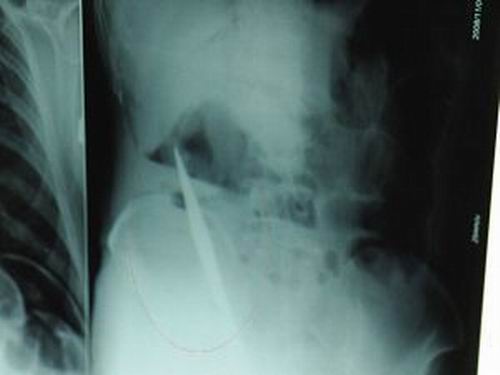

X光片上,尖刀清晰可見。

從男子體內(nèi)取出的尖刀足足有19厘米長。

江蘇銅山一58歲男子因服毒被送到醫(yī)院搶救,可醫(yī)生采取搶救措施后卻發(fā)現(xiàn)效果不佳。后來經(jīng)細致檢查,醫(yī)生有了個驚人的發(fā)現(xiàn),該男子的體內(nèi)竟然有一把尖刀,醫(yī)生通過手術將位于其腹部右側橫結腸下緣的尖刀取了出來。這把尖刀足足有19厘米長!據(jù)醫(yī)生推測,這把刀應該是從肛門推進體內(nèi)的,不知男子為何想以如此殘酷的方式結束自己生命。由于搶救及時,該男子已暫時脫離危險。

昨天(11月6日)上午,記者在徐州礦務集團總醫(yī)院重癥監(jiān)護室見到了這名男子,目前他雖然已經(jīng)恢復了意識,但還不能開口說話,需要呼吸機輔助呼吸。據(jù)醫(yī)生介紹,4日中午12時左右,這名男子因服毒輕生被緊急送到醫(yī)院進行搶救,之前,這名男子已經(jīng)在當?shù)剜l(xiāng)鎮(zhèn)醫(yī)院進行了近20小時的治療,但效果不佳!安∪吮晦D院到礦總院時已神志不清,血壓極低,處于休克狀態(tài)。”救護人員給男子洗胃、初步處理以后,發(fā)現(xiàn)男子呼吸急促,于是趕緊給他拍片檢查。結果讓所有的醫(yī)生大吃一驚,竟有一把尖狀異物橫在該男子腹腔內(nèi)!當天下午5時30分,輕生男子被推上了手術臺。經(jīng)過40多分鐘的手術,該男子腹腔被打開,手術醫(yī)生發(fā)現(xiàn),男子體內(nèi)的金屬狀異物竟然是一把長19厘米的尖刀!

醫(yī)生告訴記者,手術后,醫(yī)生在病人身上并未發(fā)現(xiàn)刀痕,最后,經(jīng)過檢查發(fā)現(xiàn),在該男子直腸處找到穿孔。醫(yī)生從醫(yī)學角度分析后認為,這把尖刀應該是從肛門插入直腸的。